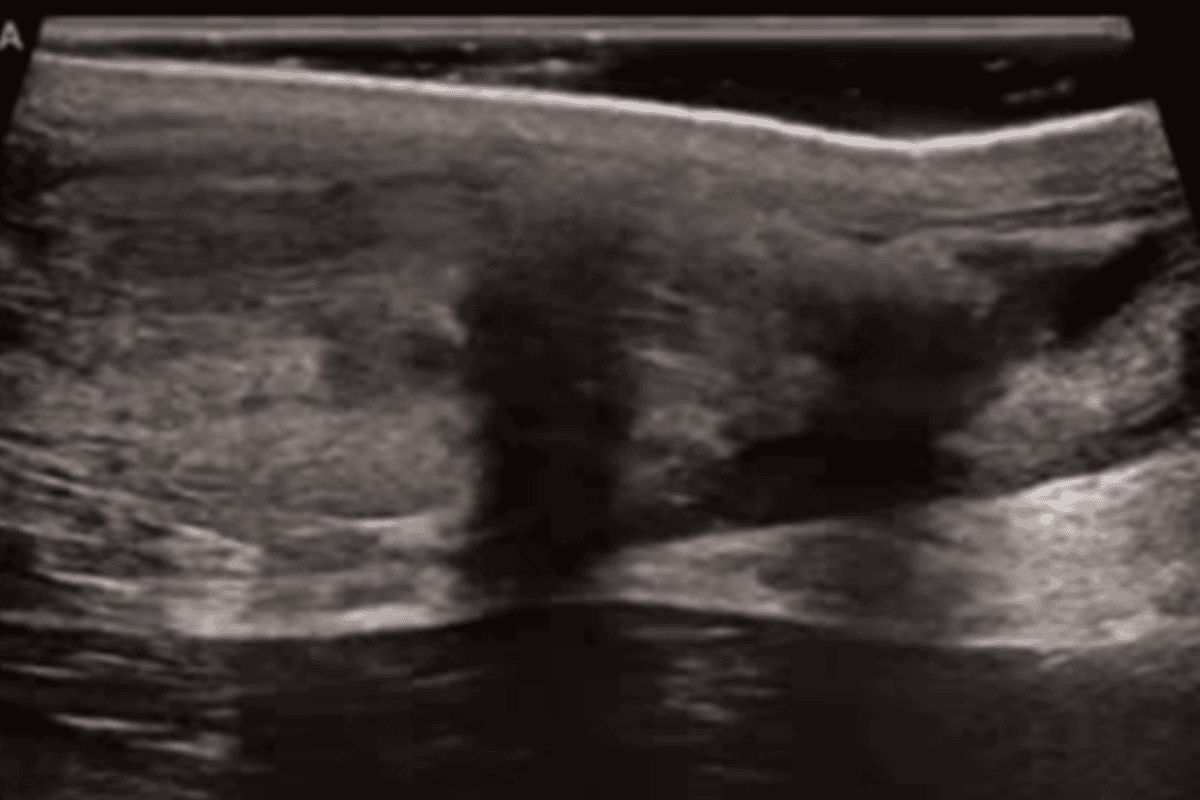

- unieruchomieniu – stopa ustawiona w zgięciu podeszwowym (orteza typu walker lub gips) przez minimum 6-8 tygodni ale często dłużej; przy takim leczeniu niezbędna jest częsta kontrola USG monitorująca zrost ścięgna;